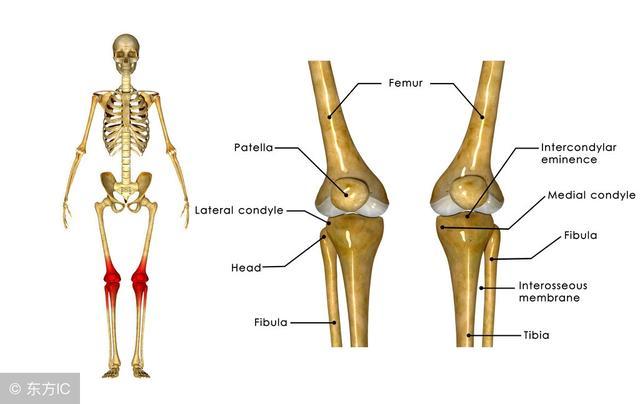

6、股骨头骨骺滑脱

膝关节的牵涉痛,儿童和十几岁的少年,膝关节疼痛的定位不清,没有膝关节外伤史,体重超重,受累髋关节轻度屈曲外旋,被动内旋和伸直受累髋关节可引发疼痛,膝关节检查正常,典型的X线表现为股骨头骨骺移位,临床表现典型但摄片阴性不能排除诊断,此时CT扫描有助于诊断。